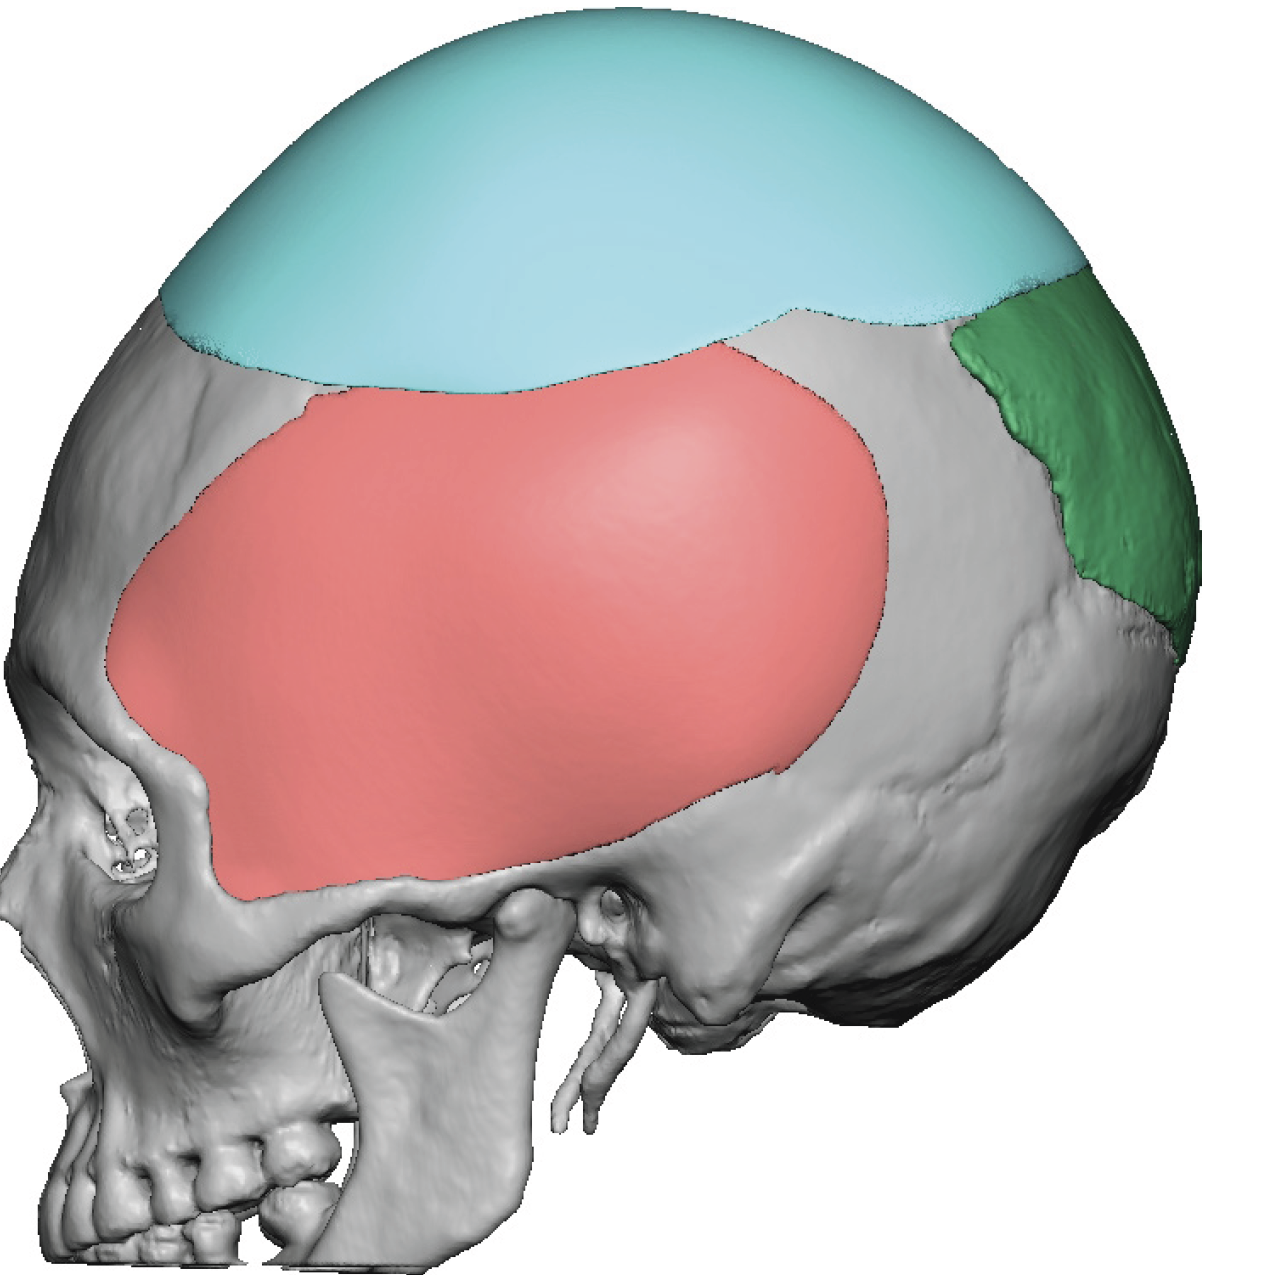

Desire for change of head shape from front view form an inverted V shape to a rounder and wider head shape.

Placement of custom extended forehead-temporal implants through incisions in the crease behind the ear. (he had a prior back of head skull implant which is green in the implant designs and which the head widening implants partially covered it)

Desire for change of head shape from front view form an inverted V shape to a rounder and wider head shape.

Placement of custom extended forehead-temporal implants through incisions in the crease behind the ear. (he had a prior back of head skull implant which is green in the implant designs and which the head widening implants partially covered it)